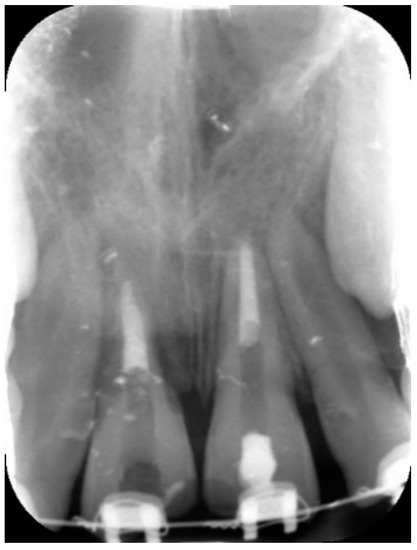

External Root Resorption Management of an Avulsed and Reimplanted Central Incisor: A Case Report

2. Case Report